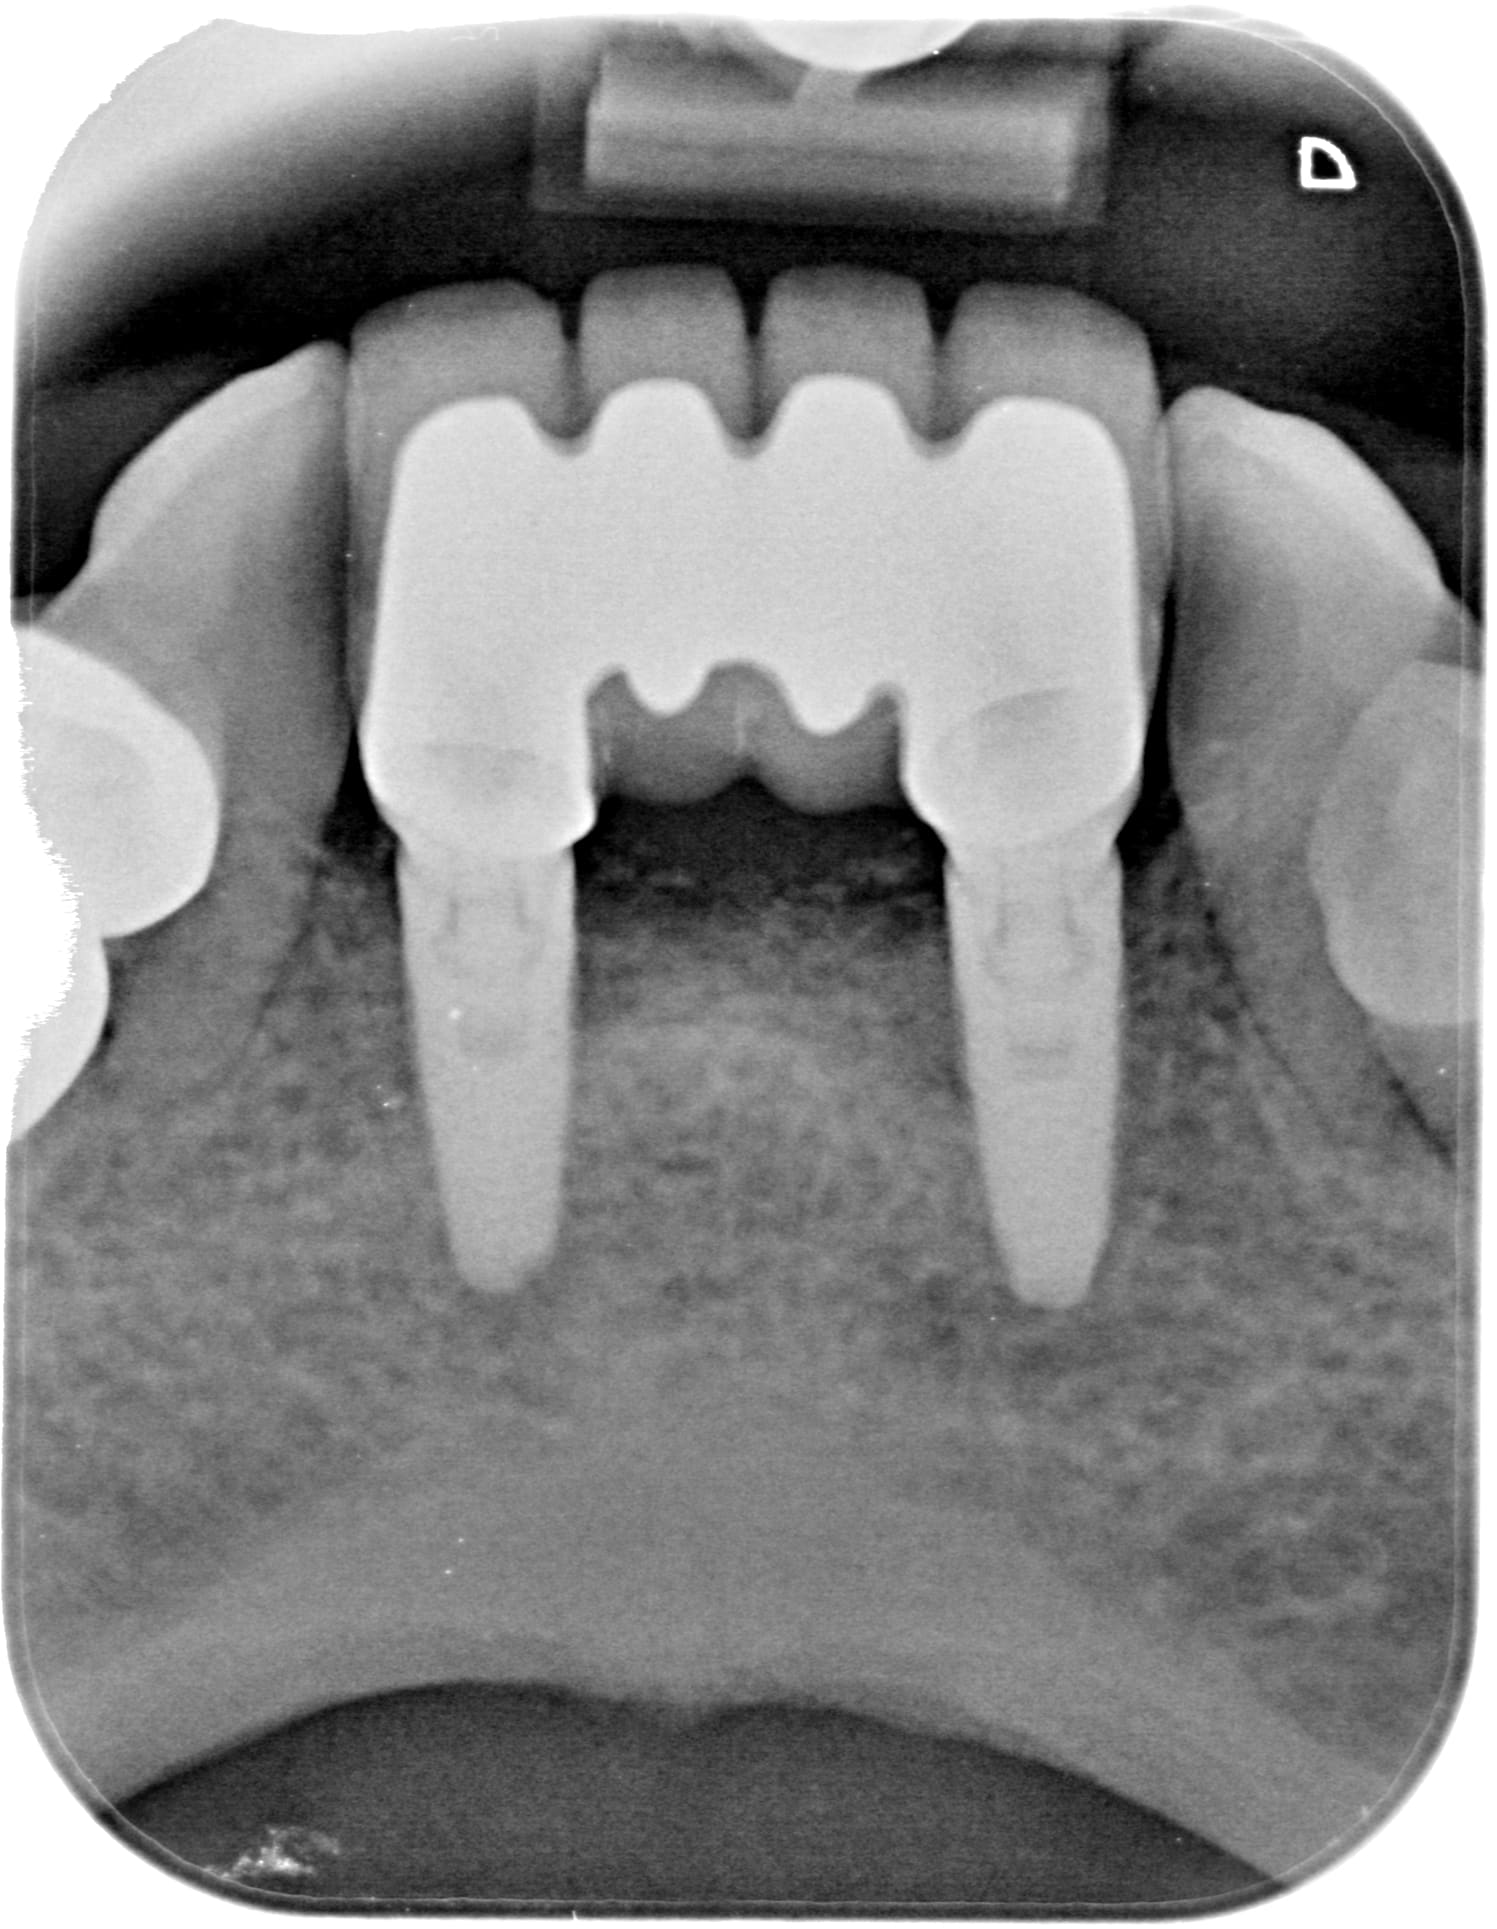

Sinon a ton avis je vais prendre combien de temps et dégager combien de BNC sur ce jeune patient de 18 ans (2bw) ? Est-ce qu'une cam a 8600e/an + 2000e/an de logiciel va m'aider ?? (60% du temps d'un omni... attention y'a un piège... ;)

Combien m'a coutée l'empreinte impregum pour le petit bridge sur implant et combien de temps de rdv ?? Sans cam a 43ke ?